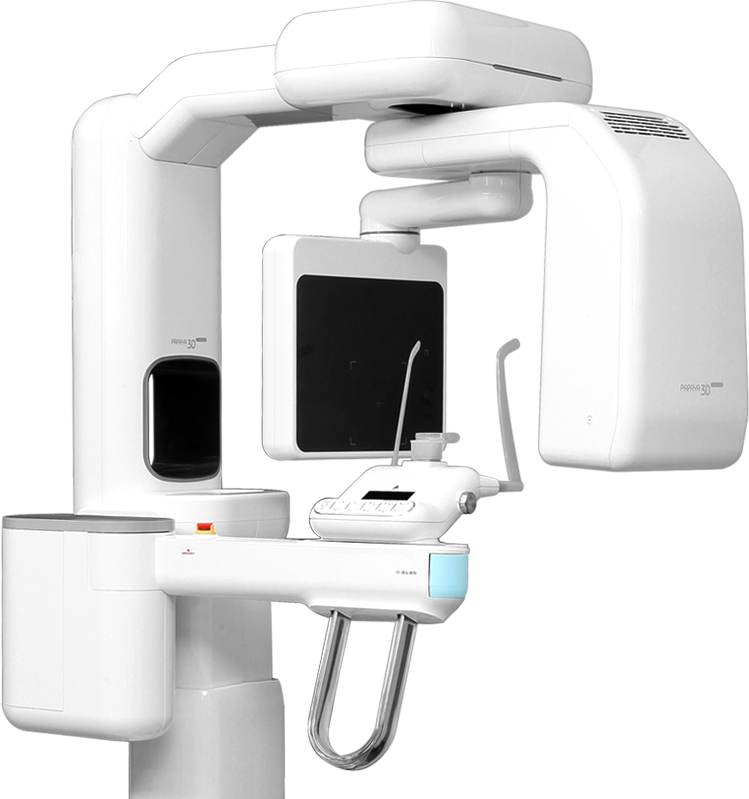

Превосходное качество изображения

- Возможность выбора автоматических программ сканирования

- Различные программы для каждого режима исследования помогут обеспечить точную диагностику

Свободный выбор зон интереса

- Свободный выбор области сканирования и разрешения.

- Получайте оптимальные снимки с минимальным облучением

Выберите самый большой сенсор

*23смХ14см и 23смХ24см

2 исследования за 1 сканирование

Благодаря функции “автоматического сшивания” вы получаете исследования всех придаточных пазух носа за одно сканированиеУлучшенная обработка изображений SMARF™

(функция подавления рентгеноконтрастности)

Существенно снижает “шум” от металлических конструкций, протезов и имплантатов для обеспечения оптимальной визуализации всех зон интереса.

Удобный доступ

Обновленная и функциональная система позиционирования пациента для любых вариантов расположения аппарата.Обеспечивает удобство для всех пациентов и экономит ваше пространство.

Комфортное позиционирование

На нашем аппарате вы позиционируете пациента сидя, это помогает врачу свести к минимуму движения пациента при проведении исследования. А так же, является более комфортным методом выбора для детей и пожилых пациентовИнтеллектуальная система позиционирования

Путем создания базы данных, на основании уже сделанных исследований, и позиционирования предыдущих пациентов, вы можете создавать быстрые и удобные сканирования без каких-либо дополнительных корректировок.